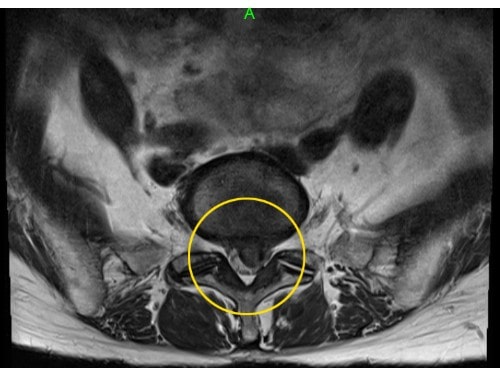

千里丘にはある全国からヘルニア患者が集まる場所が今日も誰かが痺れと向き合っている北摂でヘルニアを諦めるな※写真は患者様提供脊髄中枢神経の2/3を覆う巨大なヘルニア。何をしても痺れがある状態。でも、手術だけは絶対に避けたかった。このレベルのヘ...